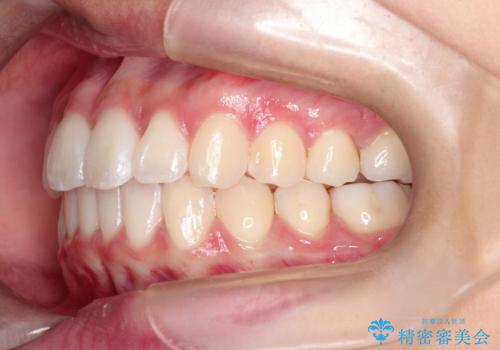

前歯のがたがたを綺麗にしたい

- 前歯がねじれていること、出ていることを主訴に来院されました。

前歯の突出感も改善され、満足していただきました。